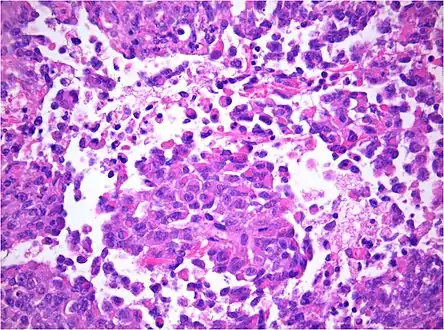

AT/RT Histology with numerous rhabdoid tumor cells

Rhabdoid Tumor Cell - 400X Magnification

Histology

The tumor histopathology is jumbled small and large cells. The tissue of this tumor contains many different types of cells including the rhabdoid cells, large spindled cells, epithelial and mesenchymal cells, and areas resembling primitive neuroectodermal tumor (PNET). As much as 70% of the tumor may be made up of PNET-like cells. Ultrastructure characteristic whorls of intermediate filaments are seen in the rhabdoid tumors (as with rhabdoid tumors in any area of the body). Ho and associates found sickle-shaped embracing cells, previously unreported, in all of 11 cases of AT/RT.[18]